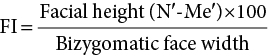

‘It is the common wonder of all men, how among so many millions of faces, there should be none alike’. Sir Thomas Browne (1605–82), English physician and writer, Religio Medici (1643)1 Individual variability is a fundamental principle in human biology. One of the most variable and distinguishable parts of the human body is the craniofacial complex. Clinicians will often compare a patient’s craniofacial measurements and proportions to the so‐called population norms (normative values) or even to classical ideals. However, Simon (1926) stated: ‘all we ever find are variations; an exact, ideal normal does not exist, cannot exist. And this is our enigma; in theory we will never find the normal, in practice we forever feel its need and apply it constantly’.2 The use of population norms may be logically enhanced by evaluating normal ranges of variability. Therefore, clinicians must have a thorough understanding of the normal ranges of variability in every aspect of craniofacial form, depending on age, sex and ethnic variability. Developmental disorders, as well as traumatic injuries and pathological conditions, may lead to deformities of the head and the face. Therefore, clinicians need to have a thorough understanding of the normal anatomy and morphological range of variation of the craniofacial complex in both males and females of different ages and ethnic groups, to act as guidelines when treatment planning the restoration of normal craniofacial proportions. Classifications that are useful for descriptive purposes include: A proportion index provides a numerical expression of the proportionality of a region of the craniofacial complex. The use of proportion indices dates back through the history of craniometry, particularly in the late nineteenth century. Linear (chord) or surface (arc) distances of the skull were measured between a variety of defined craniofacial landmarks; with any two measurements, the smaller was expressed as a percentage of the larger in order to provide a proportion index value. These could be used to provide an indication of skull shape. Figure 8.1 Determination of the normality or abnormality of any craniofacial measurement (or proportion index value) obtained from patients may be evaluated by comparison with the normative values obtained from a normal (average representative) population sample. The normal range of measurements is provided by the mean ±2 standard deviations (SD). The shape of the normal distribution curve shown is determined by the population standard deviation. Craniofacial parameters with small SDs have narrow, taller curves and those with large SDs have broader, flatter curves. Approximately 68% of all values fall within the range of ±1 SD from the mean and 95% within the range of ±2 SD from the mean. The normal range of variability for any craniofacial parameter is taken as being equal to the mean ±2 SDs. Greater differences may be perceived as deformities of gradually increasing severity. The leading researcher in the field of craniofacial anthropometry from the mid‐1960s to the early 2000s was Leslie Farkas, from the University of Toronto. Farkas et al. collected a large quantity of highly relevant anthropometric data between 1968 and 1984, from 2564 individuals.3 These data were used to provide 166 individual facial ratios, presented as proportion indices. In the creation of an index, the smaller measurement is multiplied by 100 (numerator) and divided by the larger measurement (denominator). Thus, a proportion index involves two linear craniofacial anthropometric measurements, with the smaller being expressed as a percentage of the larger. Proportion indices permit objective, quantitative assessment of facial morphology and proportions. Farkas3 identified two basic categories of proportion indices: Each proportion index will have a mean index value and a range of variation for a given population group, based on age, sex and ethnicity. The standard deviation (SD) determines the normal (average) range of variability of an index, from 2 SD below to 2 SD above the mean. Index values within this normal range are regarded as variations of normal proportions.4 Measurements within ±1 SD of the mean are regarded as optimal. The relationship between two measurements is disproportionate if the proportion index value is outside the normal range (Figure 8.1).4 For a number of facial parameters, single morphological measurements or proportion index values may have a large SD and, therefore, wide normal ranges of variation; as such, only measurements or proportion index values which differ considerably from the mean of the population will be perceived as deformities. Conversely, other facial parameters may have very small normal ranges of variability, in which case even a small difference from the mean may be perceived as a deformity. The cephalic index (index cephalicus) is a numerical expression of the ratio between the head width (biparietal diameter) and head length (fronto‐occipital diameter) of a living person. The cephalic index (CI) is calculated by the formula (Figure 8.2): Figure 8.2 Cephalic index. Where: The cephalic index is used in anthropometry to classify head types as (Table 8.1; Figure 8.3): Table 8.1 Classification of anatomical head types Index values according to Martin and Saller.5 Figure 8.3 Head types. The highest cephalic index values occur in the Chinese and the lowest values in African Americans. The larger index values of the Chinese differ significantly from those of whites or blacks (Table 8.2).6 A comparison of the cephalic index values of three ethnic groups was undertaken; North American Caucasians, northern European (German) and eastern European (Czech). The index values indicated a mesocephalic head type for both sexes of North American Caucasians and northern Europeans; and a brachycephalic (short‐wide) head type for the eastern Europeans.6 The head circumference is measured in the horizontal plane around the head, through the glabella and opisthocranion. However, it may be measured across ophyron (the point ‘On’, in the mid‐sagittal plane, of a line tangent to the upper limits of the eyebrows) rather than glabella in order to eliminate the effect of development of the frontal sinuses and superior orbital rims on head circumference.5,7 African Americans have the largest and the Chinese have the smallest head circumference for both sexes. The head circumference is slightly larger for blacks than for whites for both sexes.6 The initial step in facial analysis involves the examination of the face in frontal view in order to assess the overall facial shape. The variety of facial shapes is almost limitless. However, a simple assessment will allow an overall categorization of the basic facial shape. The basic facial shape in frontal view may be any combination of the following: Table 8.2 Cephalic index of three ethnic groups Data modified from Farkas.6 SD = standard deviation. Table 8.3 Head circumference of three ethnic groups Data modified from Farkas.6 SD, standard deviation. Figure 8.4 Facial height‐to‐width ratios. Variations in facial height and width result in an innumerable variety of the three basic facial shapes (round, square and triangular). For example, an oval facial type is a combination of an overall round face combined with increased vertical facial height and/or reduced facial width. The relationship of vertical facial height to facial width is an important indicator of overall facial shape. There are three methods of evaluating the vertical facial height‐to‐width proportion. These may be presented as proportions, percentages or indices: The facial index (index facialis or index of the morphological face height) is a numerical expression of the ratio between the facial height (nasion to menton) and the bizygomatic facial width (zygion to zygion) of a living person. The facial index (FI) is calculated by the formula: Where: The facial index is used in anthropometry to classify faces as (Table 8.4; Figure 8.6): Figure 8.5 Facial types according to Albrecht Dürer. (Modified from Dürer, 15288.) Figure 8.6 Facial types. Table 8.4 Classification of anatomical face types Index values: male according to Garson, 1885;9 and female according to Martin and Saller, 1957.5 The term facial divergence was introduced by the orthodontist‐anthropologist Milo Hellman,10 although the concept had been described by Albrecht Dürer (1528) (Figure 8.7).8 It is essentially a description of the slope or inclination of the face in the sagittal plane (Figure 8.8). It is determined by the sagittal position of soft tissue pogonion (Pog’) and subnasale (Sn) relative to a vertical line dropped from glabella (G’), with the subject’s head in natural head position. The factor that discriminates and distinguishes facial divergence from profile convexity or concavity is the sagittal position of subnasale (Sn) relative to the G’‐Pog’ line. In order for the face to diverge anteriorly or posteriorly, yet not to exhibit signs of convexity or concavity, subnasale (Sn) must be on or nearly on the G’‐Pog’ line; i.e. the upper facial plane (UFP, G′‐Sn) and the lower facial plane (LFP, Sn‐Pog’) are in a straight line, but diverge anteriorly or posteriorly. Figure 8.7 Facial divergence according to Albrecht Dürer. (Modified from Dürer, 15288.) Figure 8.8 Facial divergence. Anthropometric data from North American Caucasian males and females with untreated Class I dental occlusions describing normal facial divergence and ranges of variability has been provided.11 Mean values of facial divergence are negative, with the faces being slightly posteriorly divergent. Anterior divergence does not occur until two standard deviations from the mean. Facial divergence is essentially an ethnic variation in facial profile form. With a straight profile, i.e. no excessive profile convexity or concavity, anterior or posterior facial divergence is compatible with a normal maxillo‐mandibular and dental occlusal relationship. Figure 8.9 Facial profile contour according to Albrecht Dürer. (Modified from Dürer, 15288.) Figure 8.10 Facial profile contours. The contour of the facial profile may be described as convex, straight or concave. This concept was described by Albrecht Dürer (1528) (Figure 8.9).8 With the patient in NHP, the overall contour of the facial profile may be described by the relationship between two lines: the upper facial plane (UFP), connecting glabella (G’) to subnasale (Sn), and the lower facial plane (LFP), connecting subnasale to soft tissue pogonion (Pog’). In a straight profile, these two lines form a nearly straight line. Such a facial profile is termed orthognathic (Greek orthos: correct or straight; gnathos: jaw). An angle between these two lines indicates facial profile convexity (pogonion behind relative to subnasale in the sagittal plane), or facial profile concavity (pogonion ahead relative to subnasale in the sagittal plane). A convex profile indicates a skeletal Class II jaw relationship (and/or sagittal chin deficiency), and a concave profile indicates a skeletal Class III jaw relationship (and/or sagittal chin excess). However, profile convexity or concavity does not of itself indicate whether the maxilla or mandible/chin is at fault (Figure 8.10). Legan and Burstone12 described the angle of facial convexity for the soft tissue profile. It is formed by the two intersecting lines, the UFP (G′‐Sn) and the LFP (Sn‐Pog′). The mean value is estimated to be 12° ± 4°. An increase in the angle in a clockwise direction is positive; anticlockwise is negative. A high positive value suggests facial profile convexity and a Class II skeletal jaw relationship; a smaller positive value, or a negative value, suggests facial profile concavity and a Class III skeletal jaw relationship. However, the value of this angle does not reveal whether the maxilla or mandible/chin is responsible for the sagittal jaw discrepancy. Figure 8.11 Angle of facial profile convexity (facial contour angle). Downs13 described the angle of convexity, formed by the intersection of line nasion to point A (NA) and line point A to pogonion (A‐Pog). Superior extension of the A‐Pog line forms an angle with the NA line; if behind the NA line, the angle is read as positive, indicating a Class II (convex) skeletal profile. A negative angle of convexity indicates a Class III (concave) skeletal profile. Downs provided a range of values from −8.5° to 10°, with a mean of 0°. Again, as with the facial contour angle, the angle of convexity does not determine the localization of the deformity to the maxilla or mandible/chin. An investigation was carried out with the objective of assessing how lower facial profile convexity influences perceived attractiveness. The lower facial profile of an idealized image was altered incrementally between 14° and −16°, creating a range of images which were evaluated by pretreatment orthognathic surgery patients, laypeople and clinicians. A straight profile was perceived as most attractive and greater degrees of convexity or concavity deemed progressively less attractive, but a range of 10° to −12° was deemed acceptable; beyond these values surgical correction was desired. Patients were most critical, and clinicians were more critical than laypeople.14 The facial angle indicates the relative sagittal prominence of soft tissue pogonion. It is formed by the intersection of the true horizontal plane (or Frankfort Horizontal plane) with a facial vertical plane (N′‐Pog’). The angle should be approximately 90°–92°. A greater angle indicates prominence of soft tissue pogonion; an angle less than 90° indicates retrusion of soft tissue pogonion. The soft tissue facial angle does not of itself determine the aetiology of the sagittal position of soft tissue pogonion, which may be due to one or a combination of: Consequently, the facial angle must be used in conjunction with other measurements and analyses. In addition, when constructing the facial vertical line (N’‐Pog’), if the sagittal position of nasion is not acceptable, it may be adjusted to a more ideal position. The alternative is to use soft tissue glabella (G’) rather than nasion. Downs13 described the facial angle as the inferior inside angle in which the facial line (N‐Pog) intersects the Frankfort Horizontal plane. Downs found a mean value of 88° with a range of 82°–95°. It indicates the relative sagittal position of the mandible/chin to the upper face. Figure 8.12 Facial angle. FH, Frankfort Horizontal plane; TrH, true horizontal plane. Figure 8.13 The relationship of the cranial base angle (saddle angle) and anterior cranial base length on the jaw relationship. The relationship of the anterior to the posterior cranial base is of particular importance in the diagnosis of facial profile contour. This relationship depends on the extent of growth at the sphenoethmoidal and spheno‐occipital synchondroses. The cranial base angle (or saddle angle) represents the orientation of the anterior cranial base (SN line) relative to the posterior cranial base (S‐Ba line).15 The average adult values (bearing in mind that there is negligible change in this angle after the age of six years) for the angle N‐S‐Ba are16: As such, the cranial base angle is an important determinant of craniofacial form, as it influences the sagittal position of the face relative to the neurocranium and the sagittal prominence of the mandible relative to the maxilla. A significantly increased cranial base angle contributes to a skeletal Class II jaw relationship, whereas a reduced cranial base angle contributes to a skeletal Class III jaw relationship. If basion is difficult to identify on a lateral cephalometric radiograph, articulare may be used instead, i.e. the posterior cranial base is drawn between sella and articulare. The average adult values for the angle N‐S‐Ar are16: The anterior cranial base length, measured from sella to nasion, may also influence the jaw relationship. For example, increased anterior cranial base length may lead to a Class II jaw relationship, with the maxilla ahead of the mandible in the sagittal plane, whereas reduced cranial base length may lead to a Class III jaw relationship, with the maxilla behind the mandible in the sagittal plane. The average adult values for the anterior cranial base length are16: Figure 8.14 Parasagittal profile contour. An additional and extremely important consideration is the description of the parasagittal profile (Figure 8.14). It is necessary to evaluate the sagittal relationships of the soft tissues from the infraorbital area to the paranasal area to the parasymphyseal area. For example, maxillary hypoplasia may lead to lack of bony support and flattening in the infraorbital region and paranasal hollowing; with a normal parasymphyseal area, this will lead to the appearance of a concave parasagittal profile. The directional pattern of facial growth has a significant effect on facial profile form. Deviations from the normal pattern of jaw growth may be in a predominantly vertical or horizontal direction. Alternative terms are hyperdivergent facial growth pattern (referring to the excessive divergence of the maxillary, occlusal and mandibular planes in relation to each other and to the anterior cranial base).17 Such a pattern of growth leads to a hyperdivergent facial type, alternatively termed a high angle patient (referring to the increased mandibular plane angle), long face deformity or long face syndrome.18 If the hyperdivergent growth is the primary aetiology to an anterior open bite, the terms skeletal open bite or apertognathia (Latin apertus: open; Greek gnathos: jaw) may be used.19,20 The maxilla rotates downward and backward (posterior vertical maxillary excess), as does the mandible during growth. This leads to reduced sagittal projection of the chin. Such a vertical facial growth pattern will tend to be associated with a posterior pattern of mandibular growth rotation. Figure 8.15 Hyperdivergent, ‘high angle’ facial type.

Proportion indices

Facial index

Face type

Facial index

Males

Females

Hyper‐euryprosopic (very broad, short face)

≤78.9

≤76.9

Euryprosopic (broad, short face)

79.0–83.9

77.0–80.9

Mesoprosopic (normoprosopic; average face)

84.0–87.9

81.0–84.9

Leptoprosopic (tall, narrow face)

88.0–92.9

85.0–89.9

Hyper‐leptoprosopic (very tall, narrow face)

≥93.0

≥90.0